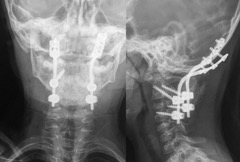

- Figura 7. Radiografías Post revisión AP y Lateral